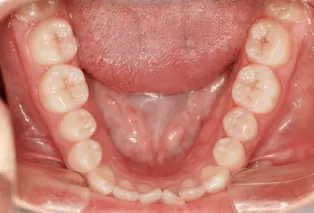

Intraoral photos